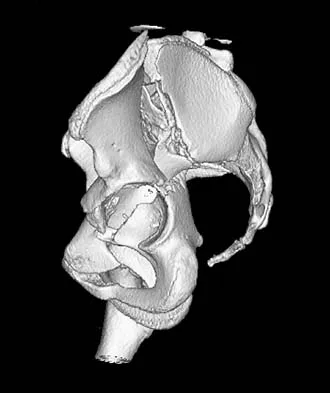

Question 72

A 22-year-old right hand-dominant man who fell off his motorcycle onto the tip of his right shoulder 2 weeks ago now reports pain and difficulty raising his right arm. Examination reveals tenderness and gross movement over the lateral scapular spine and severe weakness during resisted abduction. A radiograph and 3D-CT scan are shown in Figures 24a and 24b. What is the next most appropriate step in management?

Explanation